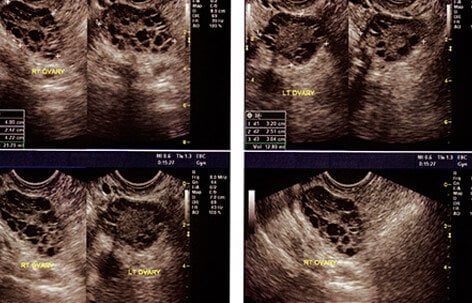

Pelvic and Transvaginal Ultrasound

Ovarian cysts are often detected during a pelvic exam. A pelvis ultrasound can allow the doctor to see the cyst with sound waves and help determine whether it is comprised of fluid, solid tissue, or a mixture of the two. A transvaginal ultrasound consists of a doctor inserting a probe into the vagina in order to examine the uterus and ovaries. The examination allows the doctor to view the cyst in more detail.